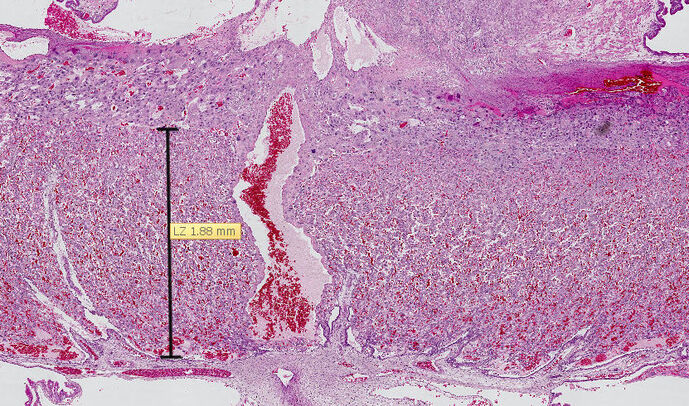

Placenta de rat (Sprague Dawley) au 21ème jour de gestation, coloré à HE (l'hématoxyline et l’éosine). La zone mesurée est le labyrinthe où se trouve le réseau capillaire placentaire.

L’UMR PHAN s’intéresse depuis plusieurs années à la citrulline, un acide aminé non essentiel et non incorporé dans les protéines, présent dans le sang à l’état normal. La citrulline est un précurseur de l’arginine, un autre acide aminé connu pour ses propriétés vasodilatatrices et donc susceptible de favoriser les échanges placentaires. Sur un modèle animal de RCIU induit par un régime maternel pauvre en protéines, l’UMR PHAN a montré qu’une supplémentation en citrulline pendant la gestation chez le rat augmente le poids des fœtus et stimule la synthèse protéique au niveau des muscles. Au cours de sa thèse, Nhat-Thang TRAN a étudié en détail les effets de la citrulline au niveau du placenta. Il a montré que la citrulline stimulait la fonction placentaire en agissant sur l’expression de plusieurs gènes. En particulier, la citrulline augmente l’expression du gène Igf2, codant un facteur de croissance jouant un rôle majeur dans la croissance fœtale et placentaire. La citrulline stimule également l’expression de gènes impliqués dans la vascularisation du placenta et dans le transport des acides aminés de la mère vers le fœtus.

Ces résultats ont permis de préciser que les effets bénéfiques de la citrulline sur la croissance fœtale pouvaient s’expliquer, du moins en partie, par une amélioration de la fonction placentaire. Les travaux menés dans l’UMR PHAN sur la citrulline permettent d’envisager des essais cliniques sur cet acide aminé dans le traitement ou la prévention d’anomalies placentaires aboutissant à un RCIU.